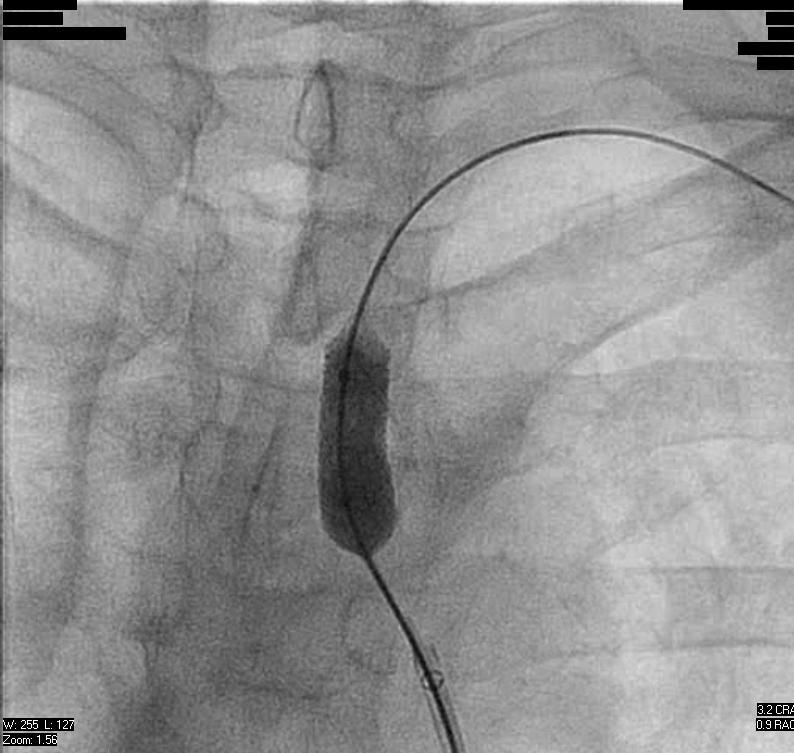

At this point, the balloon would not deflate and could not be retracted into the sheath. Attempts to aspirate and dilute the contrast in the balloon were unsuccessful. Though a wire was passed around the balloon, it could not be snared. After some deliberation, it was decided to pull the balloon back to the brachial artery (Figure 3):

Under ultrasound guidance, a micropuncture needle was advanced into the mid-body of the balloon. Aspiration of the needle did not yield blood or contrast material, though on fluoroscopy the balloon appeared deflated and was then able to be pulled back into the sheath. Final angiograms showed mild spasm in the brachial artery without apparent arterial injury and the patient had an uneventful recovery. This event was reported to the manufacturer, which promptly initiated a recall of this balloon from its product line.